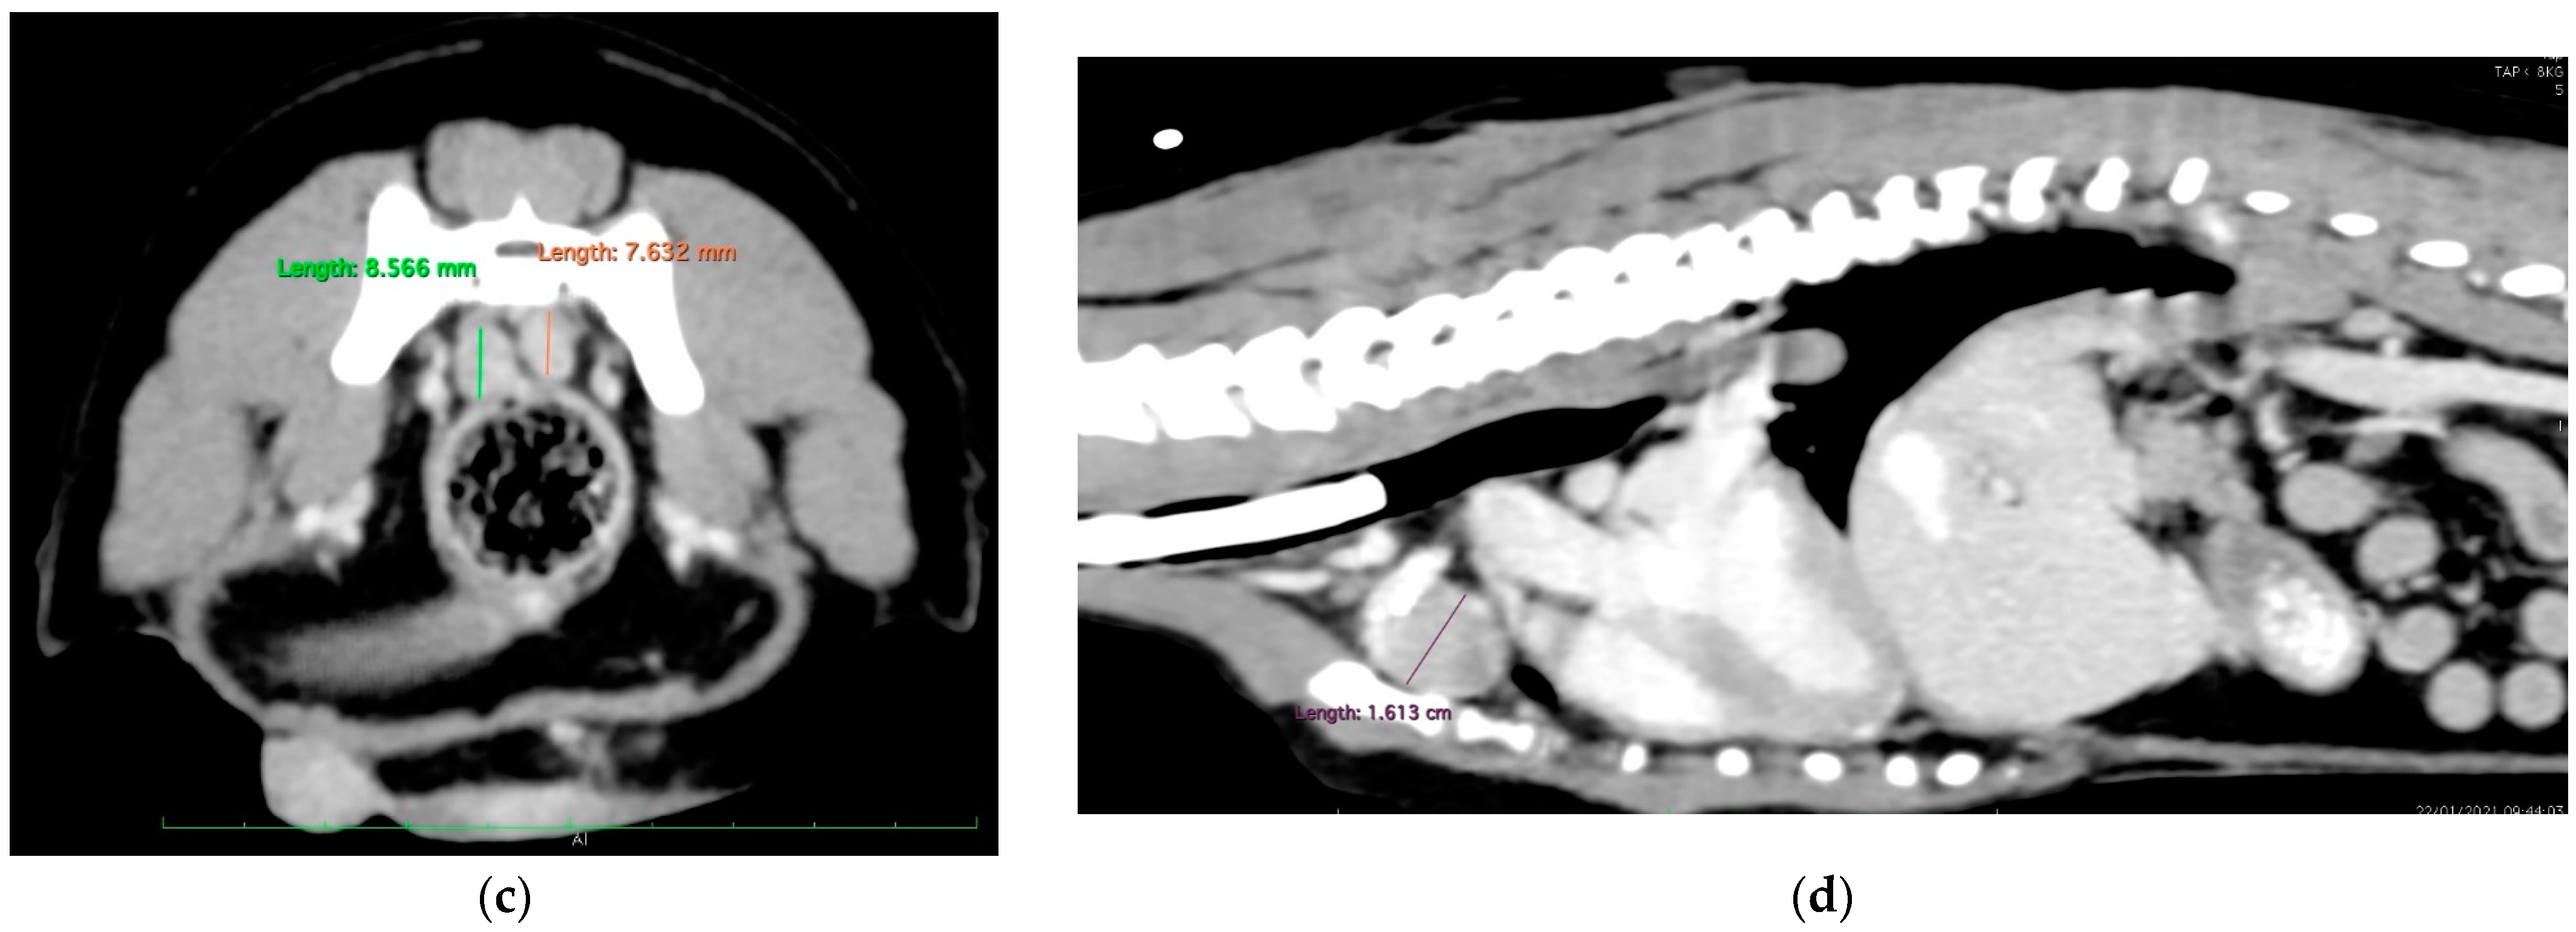

3.2. Additional Medical Tests

| 1 September 2021 | flaccid tail, evolving into posterior paresis within 24 h, spinal metastasis (CT examination) | ||||||||